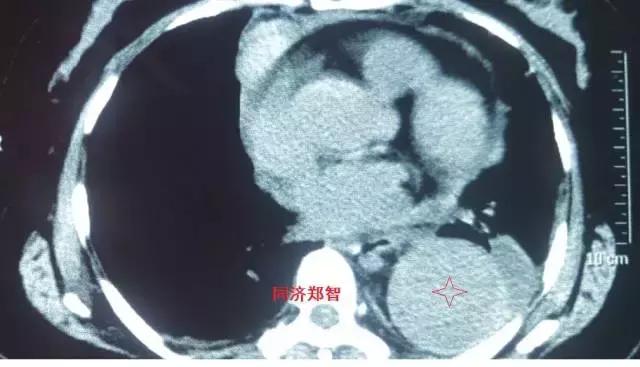

病例三

胸部平扫CT提示胸降动脉增宽(红色星形标记),CTA证实B型主动脉夹层伴降主动脉夹层动脉瘤形成。